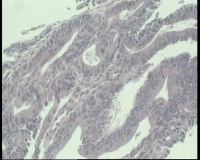

性别

女

年龄

43岁

临床诊断

结肠CA

一般病史

进镜达横结肠近肝曲,见不规则增生性肿物,环周生长,表面充血糜烂,触之易出血,肠腔狭窄,镜身无法通过

标本名称

肠镜活检

大体所见

肠镜活检4块

镜下腺体异型小,纤维间质反应,能直接报结肠腺癌吗?

可一类报告报:管状绒毛状腺癌

高-中分化腺癌。